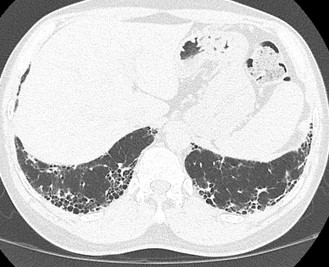

Figura 1A e B: Paciente com fibrose pulmonar idiopática mostrando franca progressão da doença nos exames de imagem de seguimento com diferença de 1 ano. Note a maior extensão do reticulado, bronquiectasias, bronquiolectasias e do faveolamento em B.